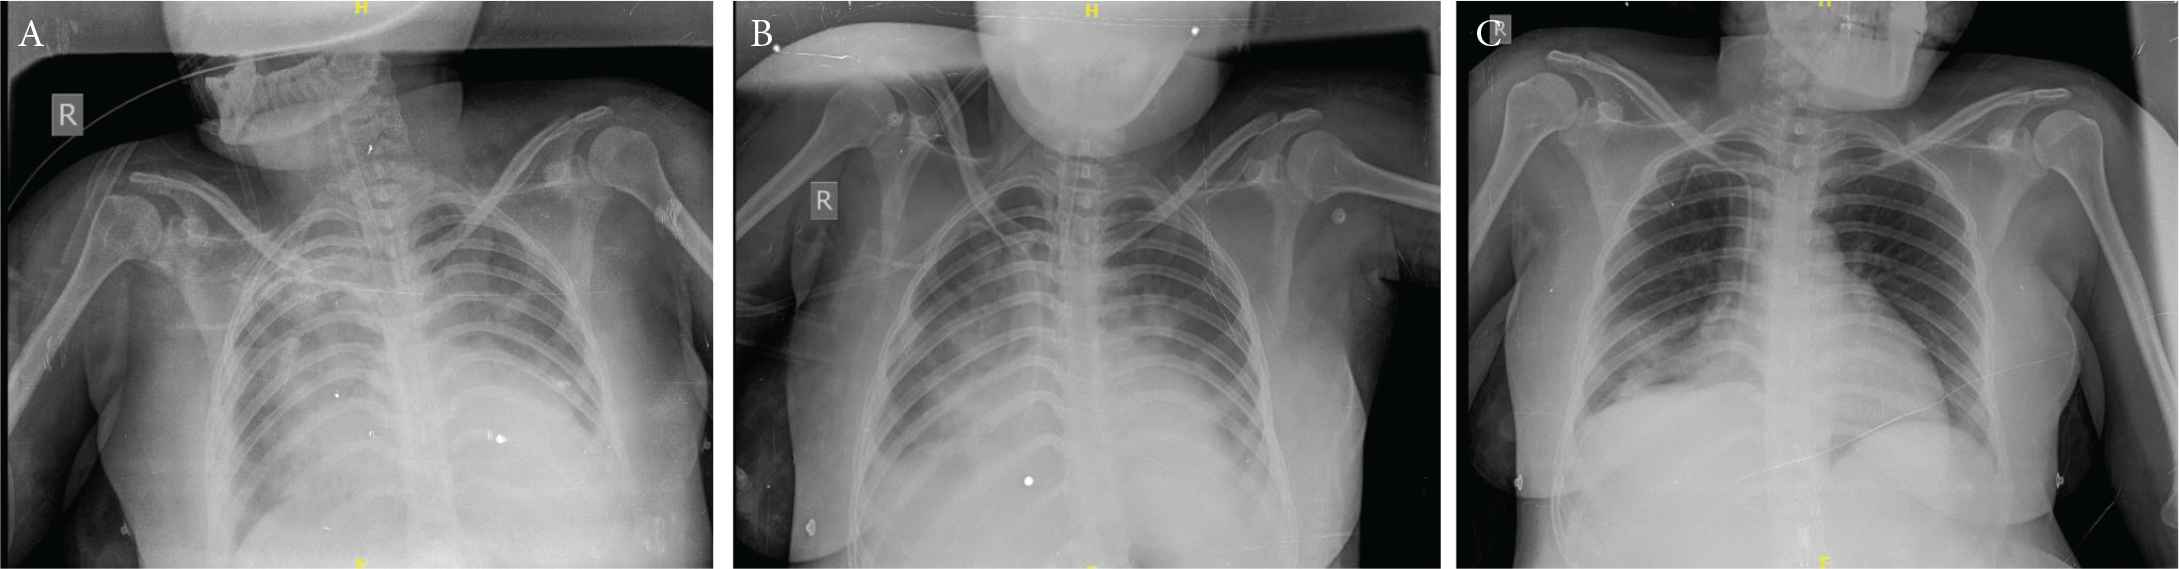

Her immediate post-operative haemoglobin was 8.5 gm% and platelet count was 1.5 lakhs but haematuria persisted. She therefore received fresh frozen plasma 25 ml/kg body weight 8th hourly and intravenous fluids at 20 ml/h and intravenous furosemide 40 mg 12 hourly. She was started on intravenous piperacillin 4.5 g 12 hourly, amikacin 375 mg once daily and metronidazole 500 mg 8 hourly. Bedside X-ray chest showed features of pulmonary oedema and aspiration especially on right side (Figure 1A). Echocardiogram (ECHO) showed left ventricular diastolic diameter of 4.4 cm, global hypokinesia of left ventricle with ejection fraction of 45%. She was started on tablet enalapril 2.5 mg through ryles tube. Hypertensive crisis was managed by Nitroglycerine (NTG) infusion and dose titration done to keep the Mean Arterial Pressure (MAP) at 90–100 mmHg. Fundus examination showed grade 2 hypertensive retinopathy and there was no papilledema. Magnesium sulphate 1 g/h infusion was started on post-operative day 1. After 48 h she regained consciousness after stopping Midazolam infusion. Hypertensive crisis recurred (160/117 mmHg) despite NTG infusion. Intravenous labetalol 20 mg was given and she was sedated with midazolam again as she was restless due to the endotracheal tube block and leakage which was identified and rectified. Abdominal gaseous distension was managed by inserting dulcolax rectal pessary. Nitroglycerine was ceased after BP stabilised at 120/70 mmHg. She subsequently received oral. Amlodipine 5 mg 12 hourly, enalapril 2.5 mg 12 hourly and oral aldactone (Spiranolactone) 25 mg once daily through ryles tube. She continued to receive intravenous hydrocortisone 100 mg once daily for 3 days. She was extubated on third post-operative day and continued on nasal oxygen 4–6 L/min and Furacort (Formoterol Fumarate Dihydrate) nebulisation 8 hourly for 1 week along with chest physiotherapy. Her follow-up ECHO on third day of intensive care stay showed an improved ejection fraction (52%) and mild global hypokinesia. Chest X-rays repeated on third and sixth day of intensive care stay (Figure 1B and 1C) showed improvement in lung fields. CT brain done on fifth post-operative day (Figure 2) showed features of frontal lobe and occipital lobe oedema suggestive of PRES which was confirmed by MRI brain performed 2 days later (Figure 3).

(A) X-ray chest P/A day of admission shows ground glass appearance and early pneumonitis changes suggestive of pulmonary oedema and aspiration. (B) X-ray chest P/A; day 3 shows patches of lower lobe pneumonia right lung (following aspiration). (C) X-ray chest P/A; day 6 normal lungs.